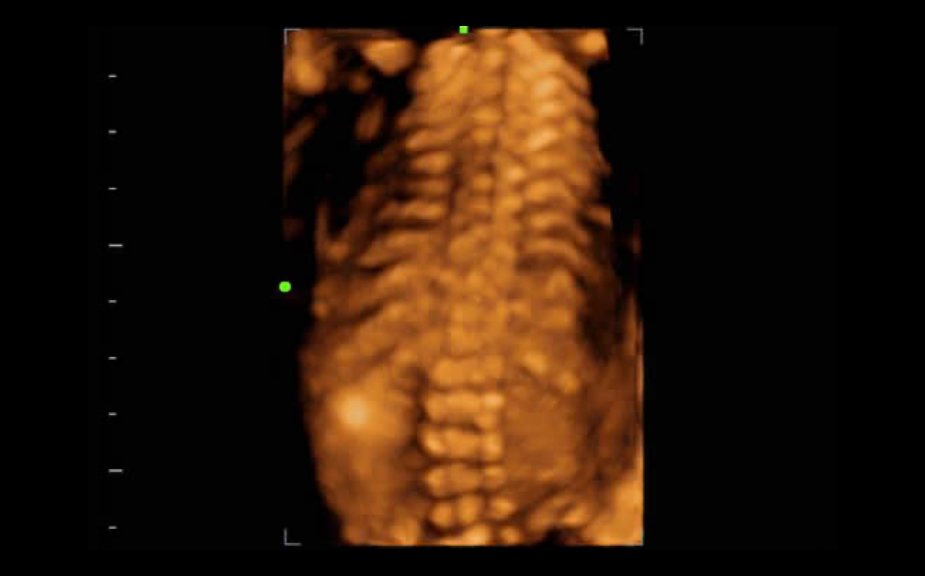

Obrazowanie 3D/4D

Z funkcjami 3D/4D Flip & Sync, kt├│re zapewniaj? szybk? i ?atw? wizualizacj? obj?to?ci obrazowanej z dowolnego kierunku

iLive

Dzi?ki integracji algorytmu rzucaj?cego promienie z now? modalno?ci? wirtualnego o?wietlenia iLive generuje niezwykle realistyczny widok p?odu, uzyskuj?c obrazy z efektem podobnym do ludzkiej sk├│ry.